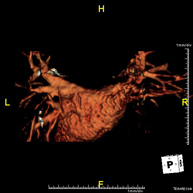

Prueba diagnóstica no invasiva que consiste en la obtención de imágenes de alta definición anatómica de las arterias cerebrales mediante el empleo de un campo electromagnético y ondas de radio (con un emisor y un receptor). No utiliza radiación ionizante. En la mayoría de los casos es necesario el empleo de contraste paramagnético (Gadolinio). Permite un estudio angiográfico no invasivo gracias a la inyección de Gadolinio con posterior reconstrucción en 2D y 3D, gracias a estaciones de trabajo especializadas. Indicaciones: malformaciones vasculares, aneurismas de arterias cerebrales, arteriosclerosis. - Angio-RM troncos supraaórticos

Prueba diagnóstica no invasiva que consiste en la obtención de imágenes de alta definición anatómica de las arterias cerebrales, mediante el empleo de un campo electromagnético y ondas de radio (con un emisor y un receptor). No utiliza radiación ionizante. En la mayoría de los casos es necesario el empleo de contraste paramagnético (Gadolinio). Permite un estudio angiográfico no invasivo gracias a la inyección de Gadolinio con posterior reconstrucción en 2D y 3D, gracias a estaciones de trabajo especializadas. Indicaciones: Malformaciones vasculares, aneurismas de arterias cerebrales, arteriosclerosis. - Angio-RM Troncos supraaórticos

Prueba diagnóstica no invasiva que consiste en la obtención de imágenes de alta definición anatómica de las arterias carótidas y vertebrales a nivel de cuello, mediante el empleo de un campo electromagnético y ondas de radio (con un emisor y un receptor). No utiliza radiación ionizante. En la mayoría de los casos es necesario el empleo de contraste paramagnético (Gadolinio). Permite un estudio angiográfico no invasivo gracias a la inyección de Gadolinio con posterior reconstrucción en 2D y 3D, gracias a estaciones de trabajo especializadas. Indicaciones: Problemas circulatorios cerebrales, síncope.